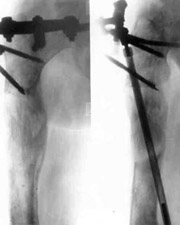

Consequences of tumour of right hip.Consequences of tumour of right hip.

Consequences of tumour of right hip.